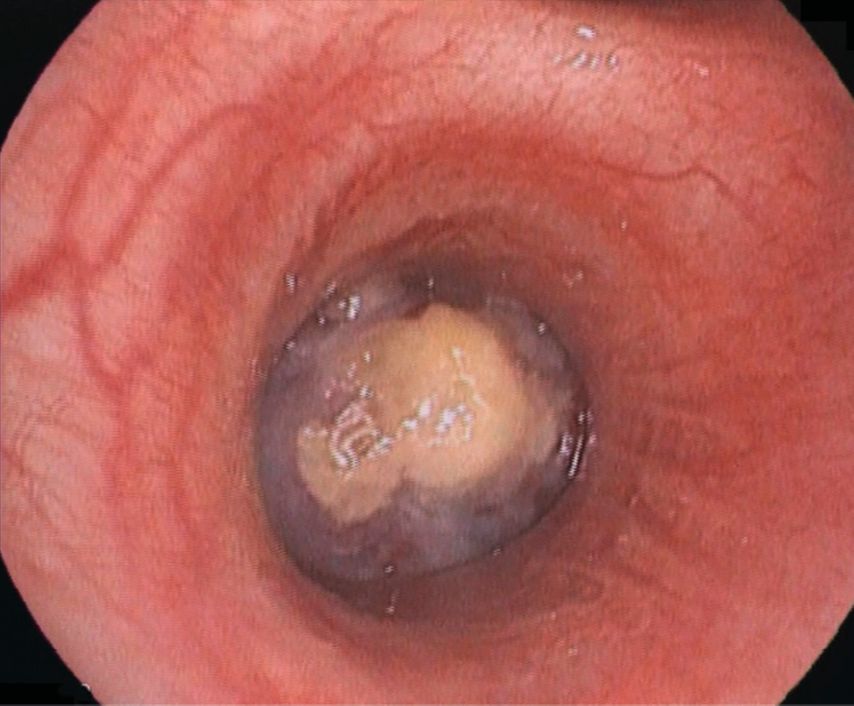

Bei der aktuellen Vorstellung wurde eine intravenöse antibiotische Behandlung initiiert, daraufhin sistierten die Hämoptysen. Thoraxsonografisch zeigte sich aber eine Persistenz der Unterlappenatelektase. In der daraufhin durchgeführten CT-Thoraxaufnahme ergab sich der Verdacht auf einen Komplettverschluss des distalen Anteils des rechten Bronchus intermedius (Abb. 2). Zur weiteren Abklärung des Befunds wurde eine flexible Bronchoskopie durchgeführt, hier zeigte sich der Befund einer endobronchialen Raumforderung (Abb. 3) mit Komplettverlegung des Bronchus, zudem waren in der endobronchialen Ultraschalluntersuchung (EBUS) suspekte Lymphknoten zu erkennen. In der gleichen Sitzung wurden aus Tumor und Lymphknoten Biopsien entnommen.

Abb. 3: Flexible Bronchoskopie, rechtsseitig, dendistalen Bronchus intermedius verlegender Tumor